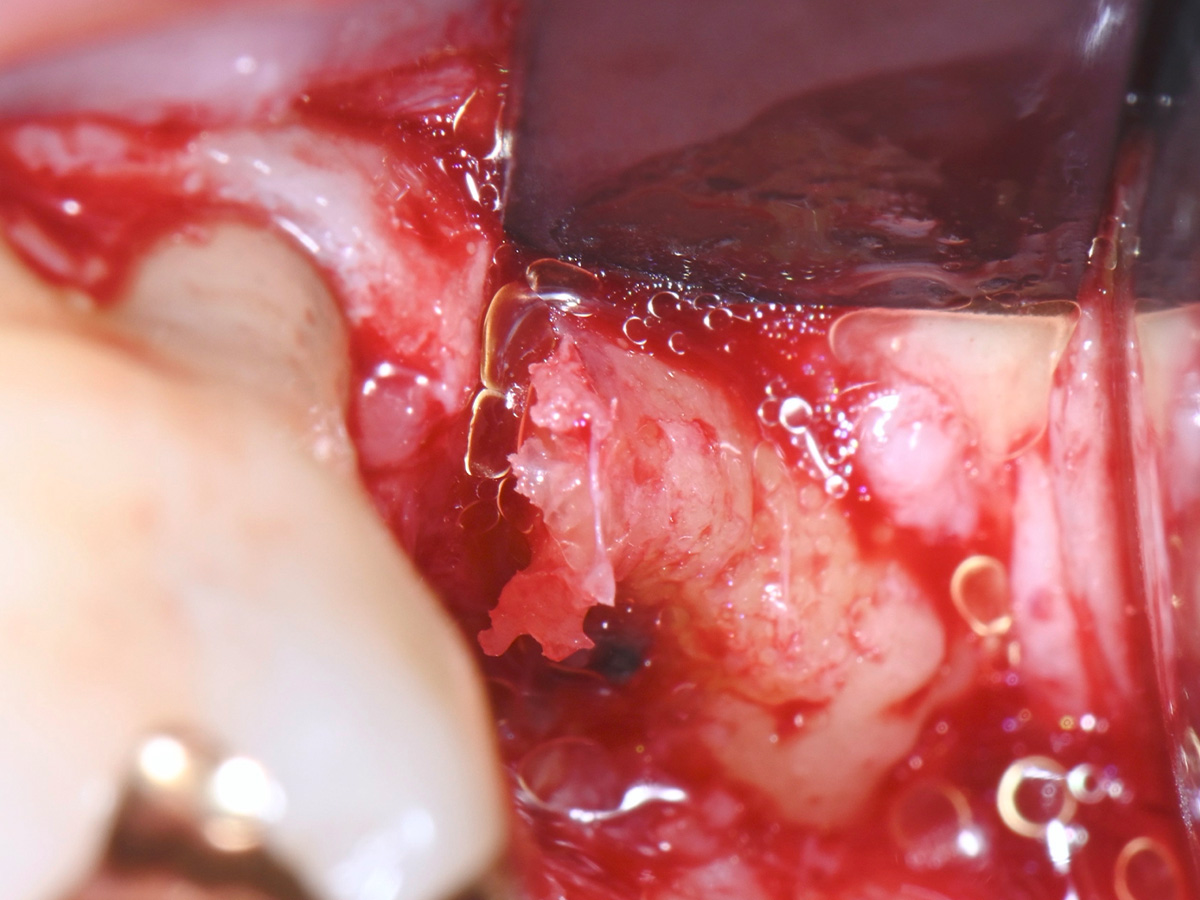

Abbildung 10

Entnahme von autologem Knochen mit einem modifizierten Knochenmeißel

Abbildung 11

Entnommener autologer Knochen aus der Tuberregion